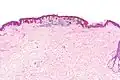

Micrograph of a dysplastic nevus showing the characteristic rete ridge bridging, shouldering, and lamellar fibrosis. H&E stain.